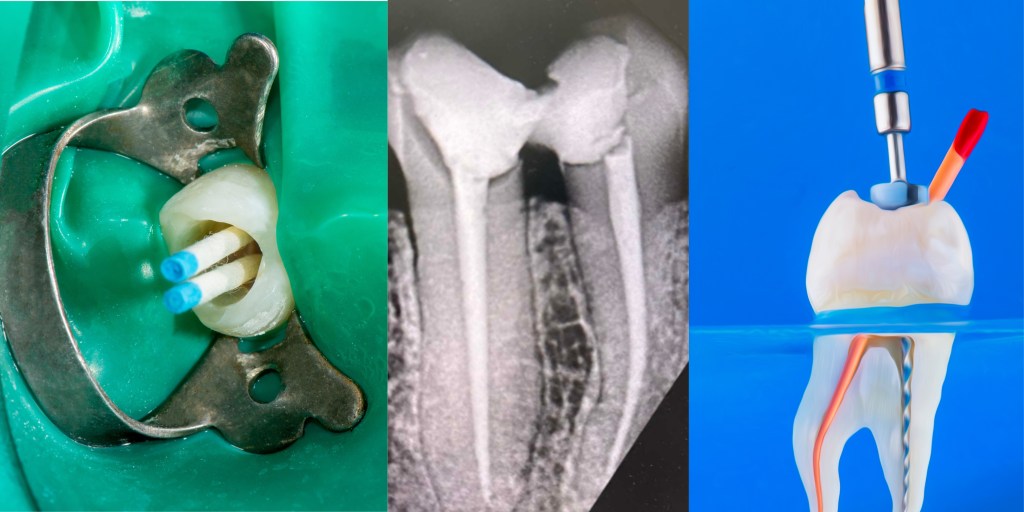

• Root canal treatment to save infected teeth

• Tooth-colored fillings for cavities

• Dental crowns for weakened or broken teeth